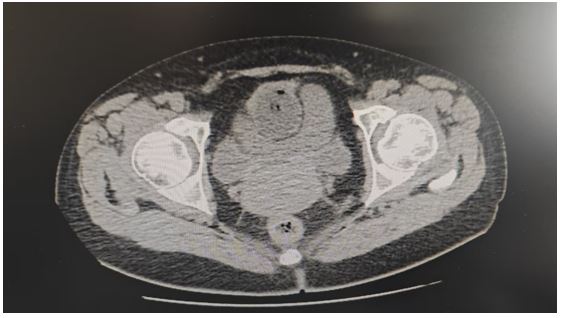

CT on April 8, 2025, post-indwelling urinary catheter placement, revealed suboptimal filling with balloon and gas shadow inside. Local protrusion of the uterus was observed. The left adnexal area showed a mass-like, heterogeneous, slightly hypodense to isodense shadow, irregular in shape, approximately 59×53 mm. The right adnexal area was full. No marked wall thickening or significant enlargement. Small amount of fluid accumulation. A left adnexal lesion was noted, recommending further clinical correlation; changes post-catheter placement; possible uterine fibroid; minimal effusion. Laboratory results showed CA-125: 88.29 U/ml (reference range 0–35), CA-199: 46.89 U/ml (reference range 0–30), while CEA, AFP, and SCC were all within normal limits. Serum amylase was 477.0 U/L (reference range 35–135), while lipase was 33.2 U/L (reference range 0–60). Liver and renal function tests were normal.